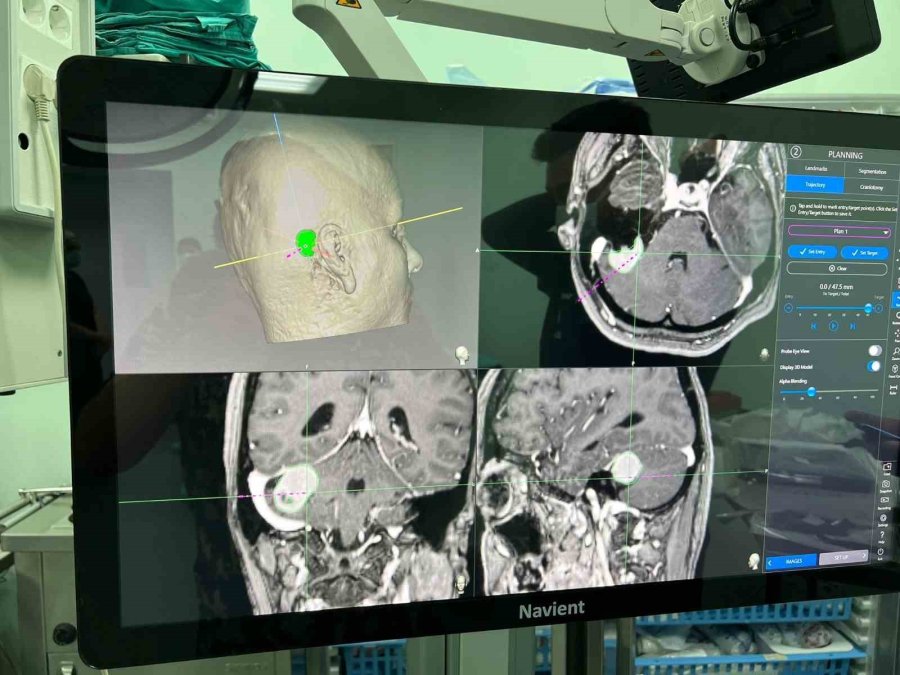

Beyin zarından kaynaklı tümörü olan hastanın 1 gün yoğun bakımda kaldığını, yarın da taburcu edileceğini söyleyen Op. Dr. Burak Yürük, "Bu ameliyatın daha konforlu, güvenli olması için yüze, yanağa ve dile giden sinirleri montize ettik. Görüntülemesini yaptık. Aynı zamanda ince kesik tetkiklerini elde ederek hem ameliyat sırasında, hem ameliyat sonrasında bize yol gösterici navigasyon dediğimiz bir haritalama yaparak tümörün tamamına yakınını boşalttık. Ameliyat sonrası filminde de hasta, mevcut baskı oluşturacak bir kitle lezyonu artık göstermiyor" diye konuştu.